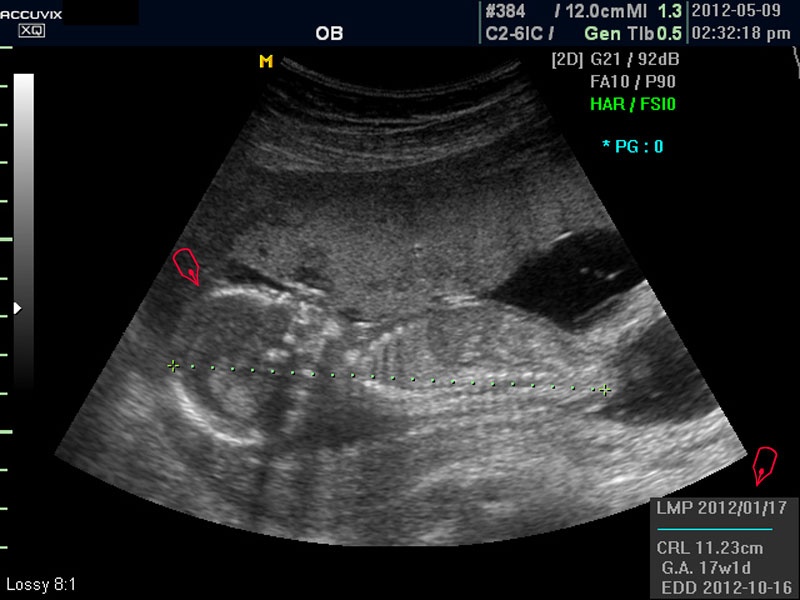

우선 초음파 사진에서 볼 것은 태아의 크기가 정상인가 하는 것입니다.

보통 태아의 발육은 머리부터 엉덩이까지의 크기인 CRL(Crown Rump Length의 약자)이 정상인가 하는 것과 태아의 두상 크기인 BPD(BiParietal Diameter의 약자)가 정상 범위에 들어 있는가 하는 것으로 판단합니다.

화면에서 좌측이 태아 머리 부분으로 빨간 펜으로 표시되어 있습니다.

초음파 상 태아의 머리가 좌측인가 우측인가 하는 것은 초음파 탐촉자의 위치를 어디에 두었느냐에 따라 다른 것 뿐으로 화면상 어디 위치하는 지는 중요하지 않습니다.

또한 이 시기는 태아의 크기가 양수에 비하여 아직 작기 때문에 자궁 내에서 하루에도 수십번 이리저리 방향을 바꾸는 시기이기 때문에 위치는 큰 의미가 없습니다.

대신 첫번째 사진에서 보는 것처럼 태아의 전체 모습 특히 태아의 등쪽이나 복벽의 이상은 없는지 신경관 결손 등으로 인한 종괴가 있지는 않은지 관찰하며 태아의 복벽이나 등쪽은 일직선으로 매끈하게 보이는 것이 정상입니다.

첫번째 사진에서는 하지 부분은 대퇴부만 일부 보이며 이는 태아가 다리를 구부리고 있고 팔도 이리저리 움직여 머리 위나 목 쪽으로 두는 경우가 많아서 한번에 전체 모습을 찍기가 어려운 경우가 많습니다.

모든 사진에서 우측 하단에는 기본적인 발육 정보가 기록되는데 세번째 사진에서 빨간 펜으로 표시한 부분이며 그 내용의 의미는 아래와 같습니다.

1. LMP

Last Menstrual Period의 약자로 최종 월경일입니다. 이런 최종 월경일을 바탕으로 현재의 임신 주수와 초음파상 측정 지표들간에 얼마나 괴리 되어 있나 하는 것을 판단하는 것입니다.

2. CRL

위에 말한 태아 크기를 말하는 지표로 실제 수치가 표시됩니다.

3. GA

Gestational Age의 약자로 우리말로는 임신 주기라고 하며 CRL이나 BPD등을 기준으로 했을때 임신 몇주 며칠에 해당하는 지 나타낸 것입니다.

5.EDD

Estimated Due Date의 약자로 초음파 측정치를 바탕으로 산출한 출산 예정일입니다.